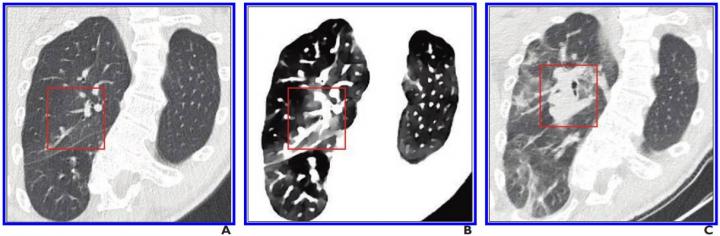

A, Initial conventional axial CT image shows no noticeable lung damage (within red box) in right upper lobe. B, Electron density spectral CT image obtained at same time as image in A shows lesions (within red box) in right upper lobe. C, Follow-up conventional axial chest CT image obtained 5 days after images in A and B confirm presence of lesions (within red box) in right upper lobe. Image courtesy of the American Roentgen Ray Society (ARRS), American Journal of Roentgenology (AJR)

October 22, 2020 — According to an open-access article in ARRS' American Journal of Roentgenology (AJR), the use of spectral computed tomography (CT) with electron density imaging could improve the assessment of lung lesion extent in patients with early-stage coronavirus disease (COVID-19).

In all four patients, their pulmonary lesions (45 ground-glass opacities, overall) were more conspicuous on electron density images than on initial conventional CT images and were clearly confirmed on follow-up conventional CT images. Moreover, lesion extent, assessed via semiquantitative reporting scale denoting surface area involvement for each lobe, was easier to ascertain on electron density images. With Daoud and colleagues' results indicating electron density imaging improves early assessment of the extent of ground-glass opacities that could be missed by conventional CT, electron density showed the most promising results by enhancing the contrast of ground-glass opacities compared with the normal lung.

"Our results suggest that the better ground-glass opacity visualization obtained using electron density imaging may be chiefly related to the increased visual noise in the image with soft kernel reconstruction and narrow lung window setting compared with electron density imaging, for which narrowing the window does not impair image quality," the authors of this AJR article concluded.